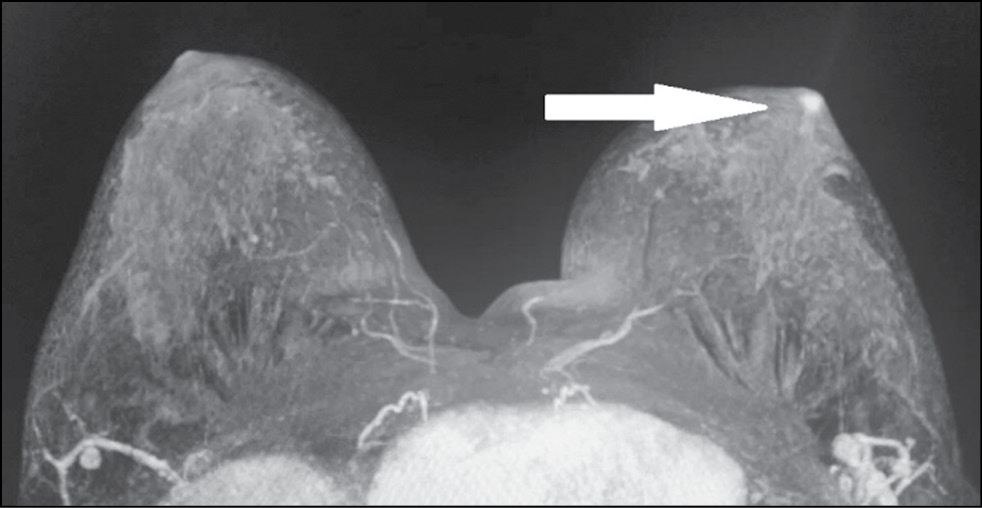

In a 43-year-old patient who had no complaints, the breast was examined by MRI to assess the integrity of implants. The asymmetric enhancement of the left nipple was accidentally found (Figs. 9 and 10). Three-year dynamic observation did not reveal any unfavorable changes.

Figure 9. Magnetic resonance imaging (early postcontrast series): asymmetric contrast accumulation in the left nipple; normal finding (arrow).

Figure 10. Magnetic resonance imaging (MIP): asymmetric contrast accumulation in the left nipple; normal finding (arrow).

Cases 3 and 4 prove that asymmetric contrast accumulation in MRI is not necessarily a sign of pathology. Normally, in MRI, both nipples accumulate the contrast agent at the same rate and intensity. However, nipple asymmetry may be the normal variation. Possible reasons include special NAC anatomy, breast size, breast compression and friction with clothing, blood flow variations, and local inflammation. [12] Aome physiological features and differences are involved in contrast accumulation in NAC structures. Both breasts usually show symmetrical thin rings of enhancement. In some cases, enhancement is asymmetrical in the early phase and becomes symmetrical in later phases. In a study of 530 normal nipples in 265 asymptomatic women, Gao et al. used T1-weighted NAC images to describe three areas of enhancement. [12]

Nipple inversion is a benign condition associated with the insufficient ability of the mesenchymal tissue to fix the nipple in the right position. [12] It occurs in 4% of women and men. Nipples are convex in 75% of women, flat in 23%, and inverted in 2%. MIP images are well suited for assessing the morphology and symmetry of the NAC. On postcontrast images, the nipple should be hypo- or isointense compared with the enhanced parenchymal tissue in the background. [12]